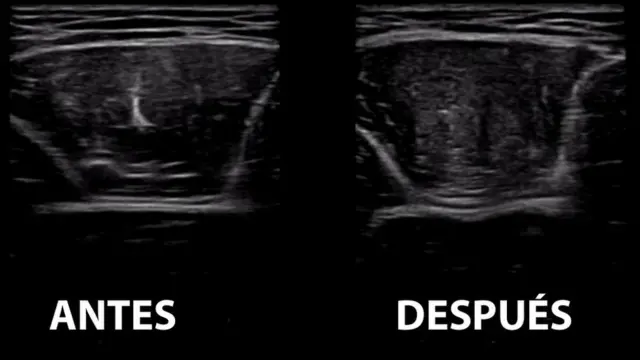

En el programa se pidió a un voluntario realizar una rutina de alta intensidad en una bicicleta, analizándose sus niveles de glucosa en el músculo de una de sus piernas antes y después del esfuerzo físico.

El doctor Niels Vollaard fue el encargado de comparar las mediciones hechas a través de una ecografía.

"Hay menos zonas oscuras en el músculo después, lo que significa que su glucógeno se redujo considerablemente, bajando hasta en un 24%", resaltó.